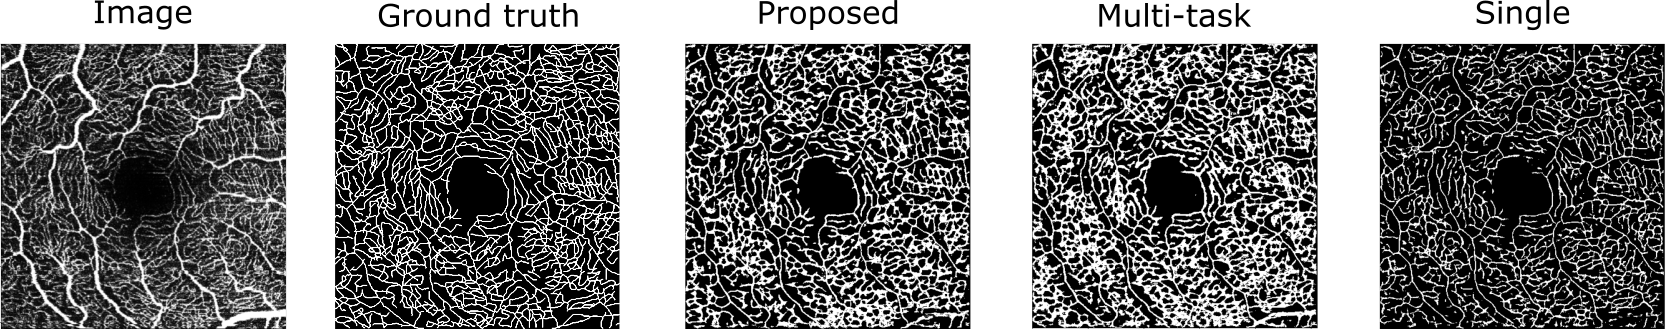

We evaluated our proposed method, OCTA-MTL, on the ROSE-2 dataset [3], and compared it with two baseline methods: a single-task segmentation method (Single Unet) [14] and a multi-task segmentation method that combined losses via an other common algorithm (Multi-task) [13]. We used the dice coefficient (Dice) and the intersection over union (IoU) scores as the evaluation metrics. Table 1 shows that our method achieved the highest Dice and IoU scores, indicating its accuracy and consistency. Figure 2 shows a qualitative comparison of the segmentation results for a sample test slice. The proposed method produced more accurate and consistent segmentation results than the other methods, as it can better capture the complex and diverse features of the vessels, while avoiding the false positives and false negatives that are present in the other methods, especially in the regions with low contrast or high noise. These findings indicate that the proposed method benefits from effective leverage of image-to-DT branch and adaptive loss combination strategy.